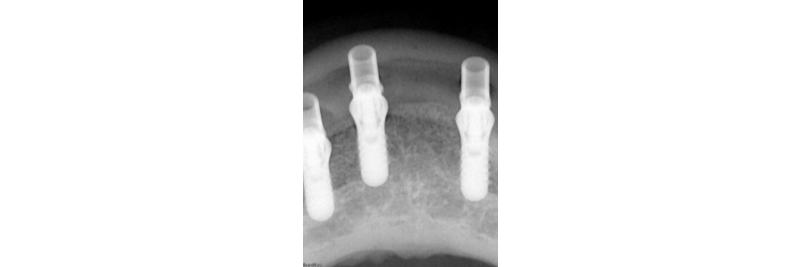

Jig fastened to the implants. One screw test is performed to confirm passivity.

Radiographic verification of the temporary cylinder fully seated on the implant platform.